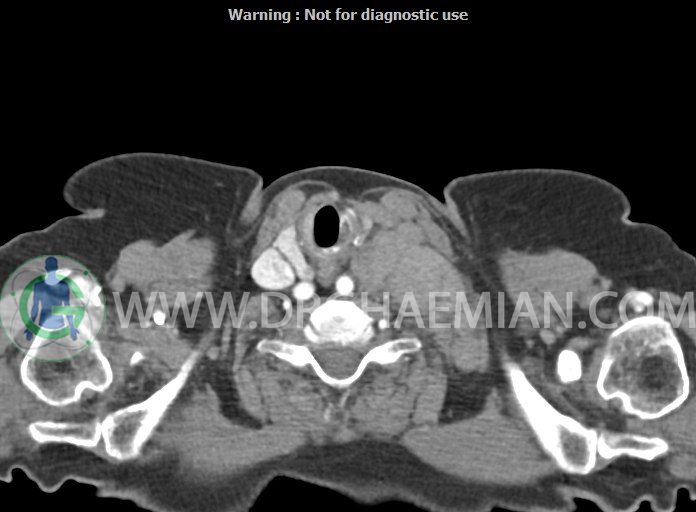

در سی تی اسکن اسپیرال از گردن با تزریق (مولتی دیدکتور 16 با مقاطع ظریف و بازسازی های ساژیتال و کرونال):

– تصویر توه های نسج نرمی oval shape متعدد با Enhancement تقریباً هوموژن، قرار گرفته در سمت چپ گردن، در لول غضروف کریکوئید با اثر فشاری شدید و compression ورید ژوگولار، با گسترش تحتانی به اینفراکلاویکولار چپ، به حداکثر ابعاد 28x50mm (با Enhancement مختصر هتروژن در این توده)

در درجه اول مطرح کننده لنفادنوپاتی متاستاتیک مطرح می باشد بالین، تومورهای منشأ گرفته از غلاف عصبی زنحیره سمپاتیک چپ گردنی، شبکه براکیال و لنفوم نیز در DDX قرار دارند. لذا نمونه برداری بافتی جهت بررسی بیشتر توصیه می شود.

– اسکولیوز مهره های سرویکال با تحدب به راست، احتمالاً در زمینه اثر فشاری توده های مذکور

مشهود است.